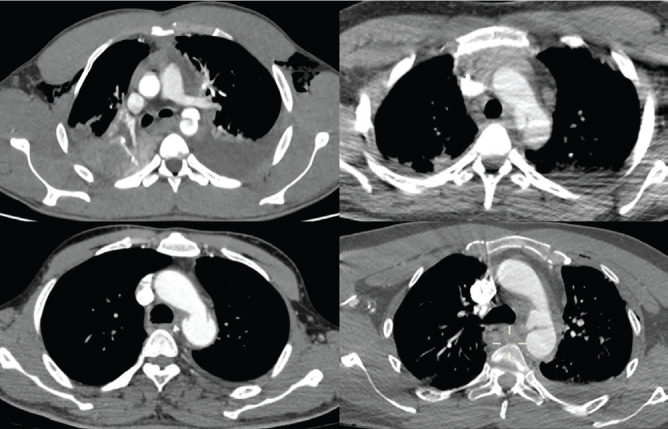

Results: All injuries were caused by high-energy traumas. Mean injury severity score was 38 and the revised trauma score was 6.58. A massive transfusion protocol was activated in 75.0% of cases. Diagnostic imaging showed varying accuracies, with computed tomography demonstrating superior sensitivity for both injuries. All TDH were left-sided posterolateral and BTAI predominantly involved the isthmus. Management followed a sequential approach, with 75.0% of diaphragmatic repairs preceding the aortic intervention. Mean hospital stay was 33 days, with complications including infections, deep vein thrombosis, and atelectasis. Despite the high severity of the injury, all patients survived.

Abstract Image